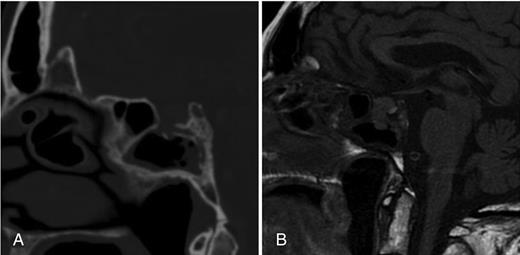

A computed tomography (CT) brain demonstrated dehiscence of the floor of the sella and mucoperiosteal thickening in the sphenoid sinus with some curvilinear calcification (Fig. 1A). Magnetic resonance imaging (MRI) brain revealed a contrast-enhancing mass within the superior aspect of the sphenoid sinus communicating with the pituitary fossa through the defect of the floor of the sella, measuring 12 mm in maximal craniocaudal dimension. The pituitary gland appeared to be heterogeneous in signal intensity on both pre-contrast T1- and T2-weighted sequences and demonstrated heterogeneous enhancement post-Gadolinium contrast administration (Figs 1 and 2). The imaging findings suggested a pituitary neoplasm with a downward growth pattern. However, the mucoperiosteal thickening in the sphenoid sinuses and the presence of calcification on CT raised the possibility of a mycetoma.

(A) Initial CT scan indicating dehiscence of the floor of the sella and mucoperiosteal thickening in the sphenoid sinus with curvilinear calcification. (B) Initial T1-weighted MRI, indicating a pituitary fossa mass communicating with the superior aspect of the sphenoid sinus.